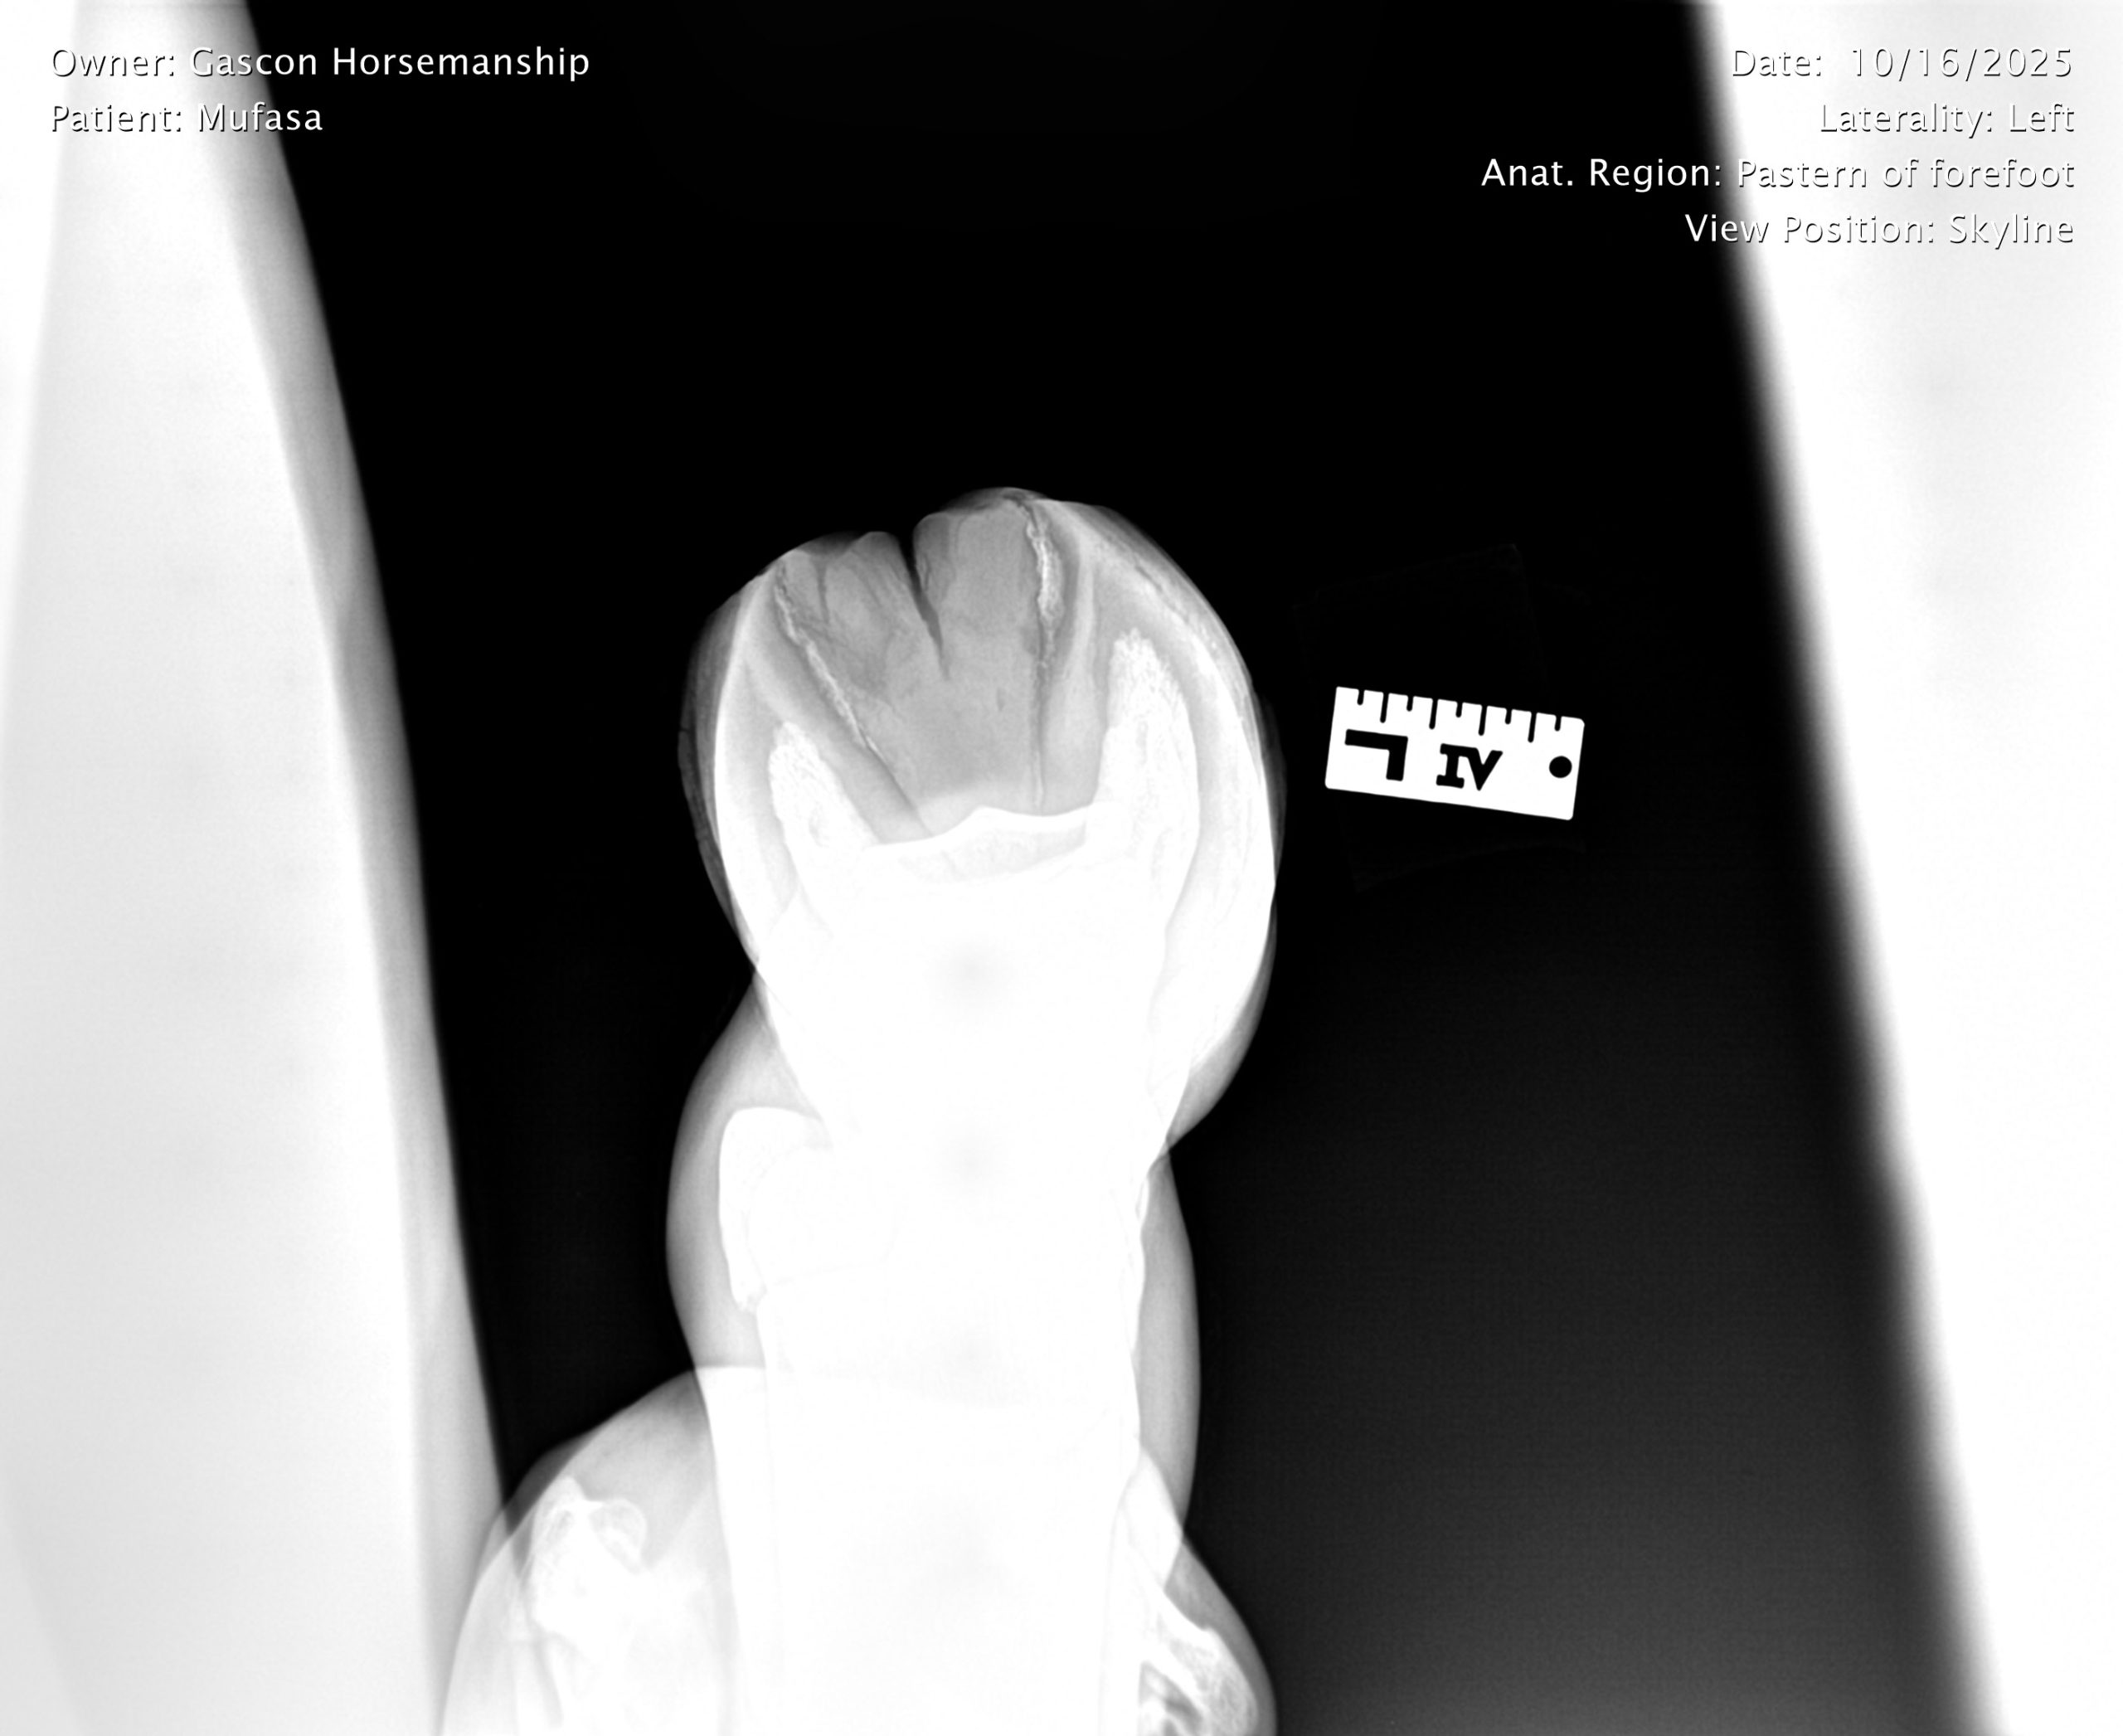

He already has a full pre-purchase exam on file, complete with 25 X-rays included in his album.